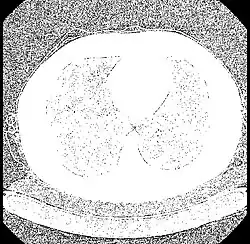

| Parenchyma | Lung | −700 to −600[25] |